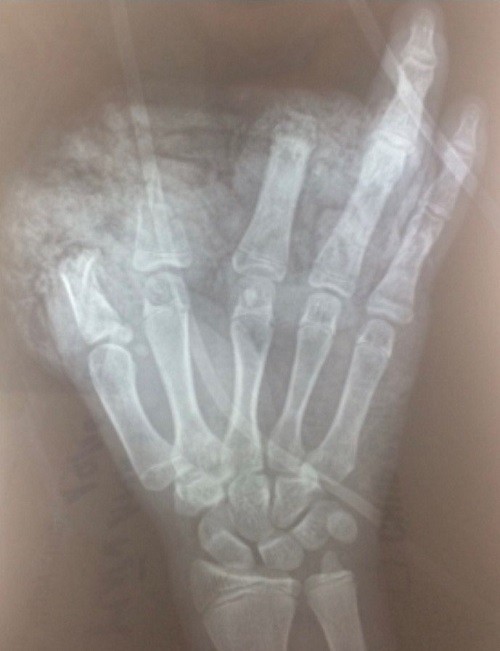

Phim chụp Xquang bàn tay trái bị cụt ngón 1,2,3 của bệnh nhi - Ảnh: BVCC

Bệnh nhi tên N.H.A.T. (nam, 14 tuổi), sống tại Trang Hạ, Thị xã Từ Sơn, Bắc Ninh. Cháu bé được đưa tới cấp cứu tại Bệnh viện Hữu nghị Việt Đức trong tình trạng nhiều xây xát vùng hàm mặt, ngực, bụng; mắt trái rách lớp mi trên, cương tụ kết mạc. Ngoài ra, bàn tay trái của cháu bị dập nát, cụt chấn thương ngón 1,2,3. Vết thương mu tay và gan bàn tay kích thước 10cm, lóc da gan bàn tay cùng nhiều dị vật đen, bẩn.

Bệnh nhi được phẫu thuật cấp cứu cắt lọc, sửa mỏm cụt ngón 1,2,3; xử lý vết thương phần mềm gan bàn tay, mu bàn tay và nhiều vị trí thương tổn khác. Ca phẫu thuật diễn ra trong 1 tiếng.